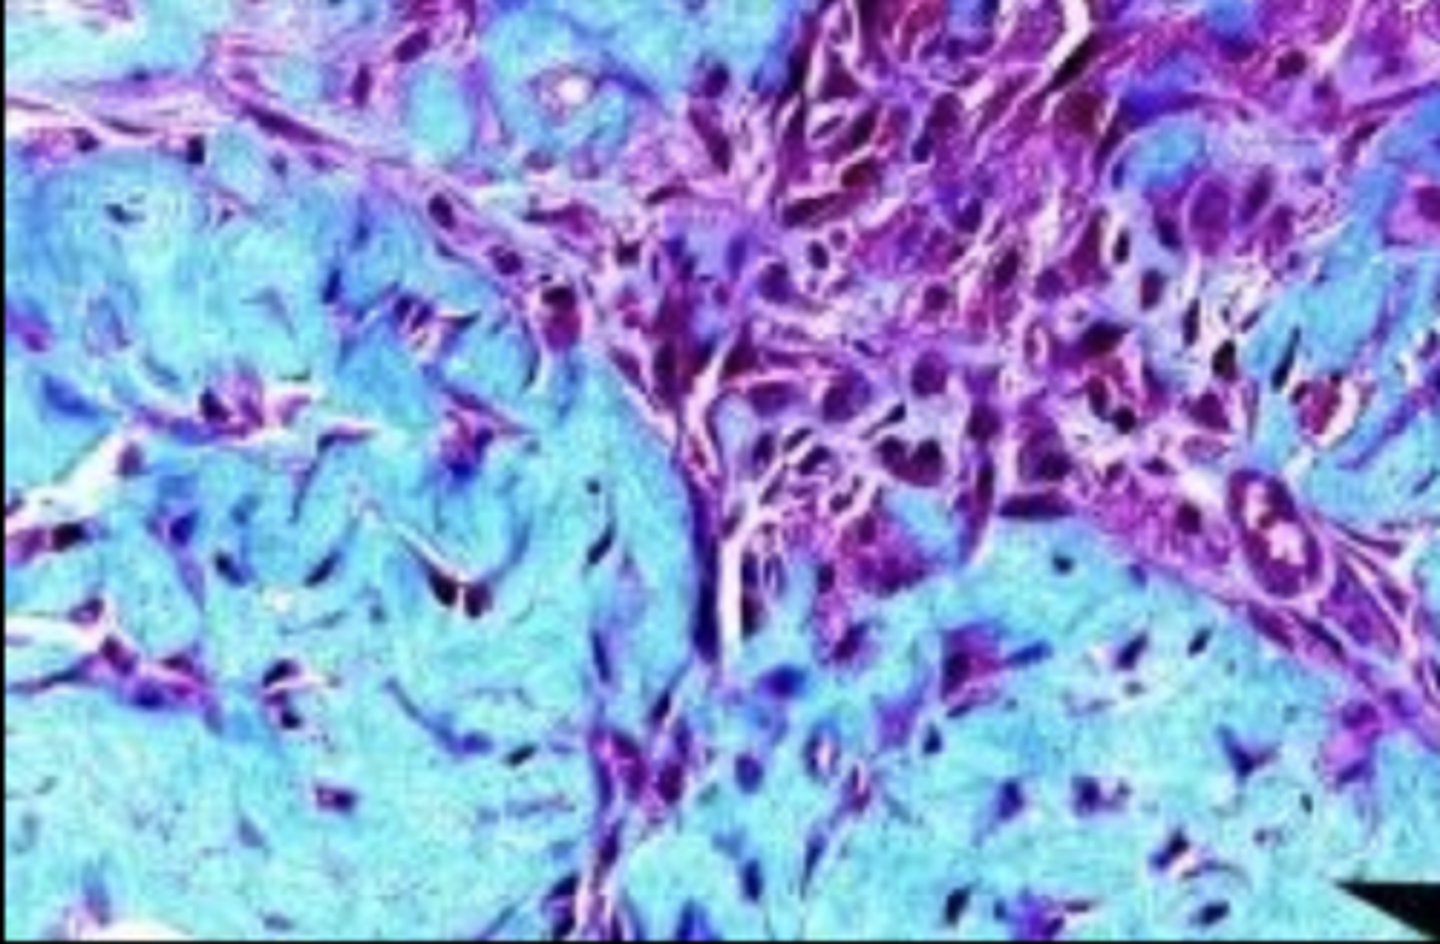

newly formed granulation tissue

mature granulation tissue